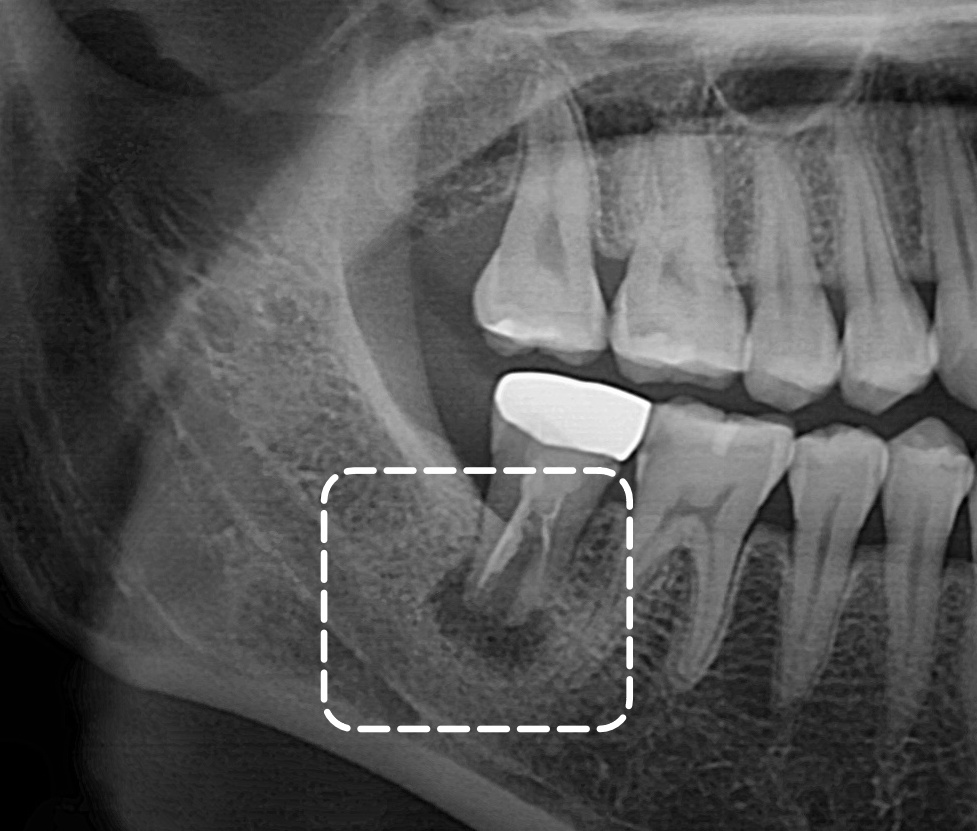

엑스레이를 보았을 때

치아 뿌리 끝 염증이 이환되어

큰 염증이 나타난 것을

관찰할 수 있는데요.

방사선 사진에서는

치근단 부위의 어두운 음영이

뚜렷하게 나타나며

주변 골조직의 파괴가

상당히 진행된 것을

확인할 수 있습니다.